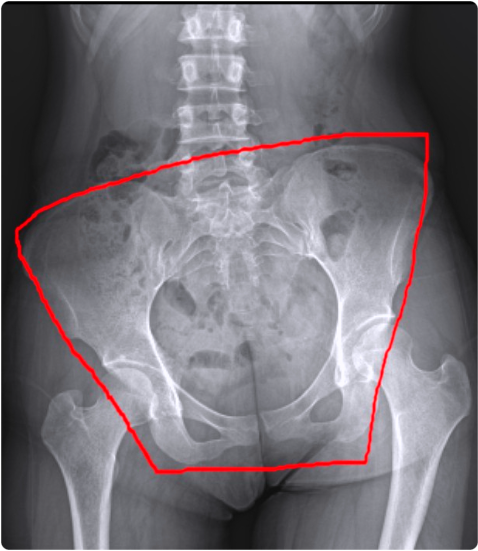

겉보기에는 티가 안 나더라도 실제로는 작은 골반 틀어짐이 문제의 시작인 경우가 많습니다.

그렇다면 평소에는 대수롭지 않게 넘겼던 골반의 불균형이 왜 이렇게 중요한 걸까요?

골반은 우리 몸을 지탱하는 가장 중요한 중심축입니다.

여기에서 조금만 기울어져도 척추, 어깨, 허리, 무릎까지 다양한 통증이 이어질 수 있지요.